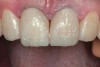

(1.) Preoperative smile photograph.

Figure 1

A 34-year-old male patient with no medical issues presented to the office with the chief complaint of a failing crown on tooth No. 12. The patient was also unhappy with his bite and the appearance of his teeth (Figure 1 and Figure 2).

The dentofacial examination revealed a low smile line with no incisor display when the lips were in repose. The anterior teeth were chipped and worn, and their overall color was darkened. The buccal corridors were deficient, and the failing crown on tooth No. 12 was visible in a full smile.